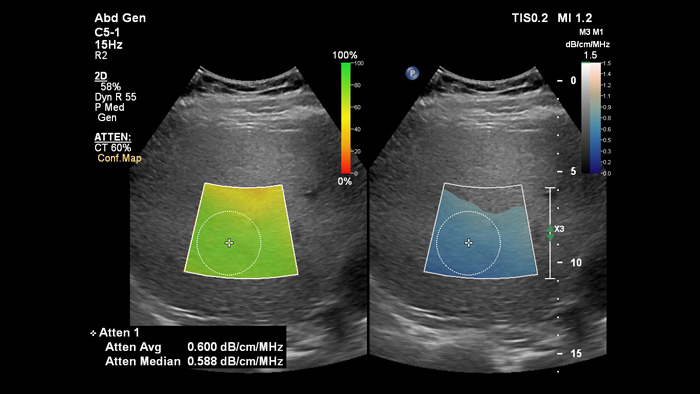

L'imaging di attenuazione può misurare la quantità di grasso presente nel fegato calcolando il coefficiente di attenuazione del suono assorbito dal parenchima epatico. Questo metodo fornisce parametri di attenuazione quantitativi che possono aiutare i medici nella gestione dei pazienti con steatosi epatica.

Imaging di attenuazione